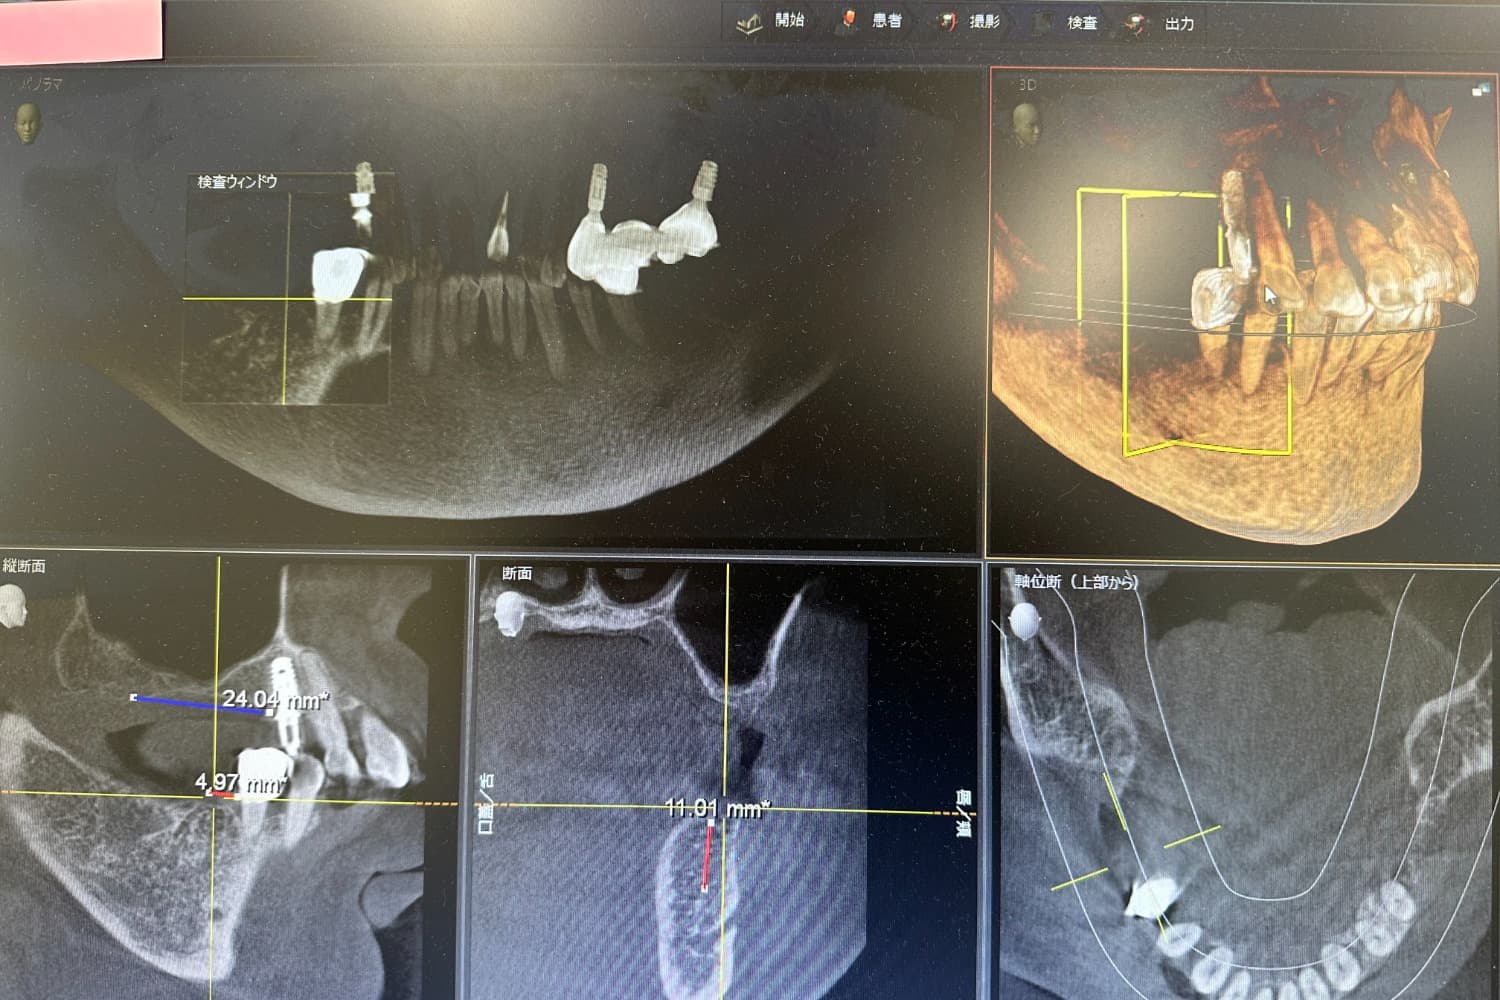

デンツプライシロナ社製アンキロスインプラントシステムを採用し、CTと3DシミュレーションSimplantを完備しています。 拒絶反応やアレルギー反応が生じない自家骨移植による防御力と免疫力を兼ね備えた自家骨骨造成BBAコンセプト、ソケットリフトやGBRなどオプションオペにより、骨が少ない難症例にも対応可能です。 インプラントは噛めて当たり前、審美性と長期安定性を追求した診療を心がけています。